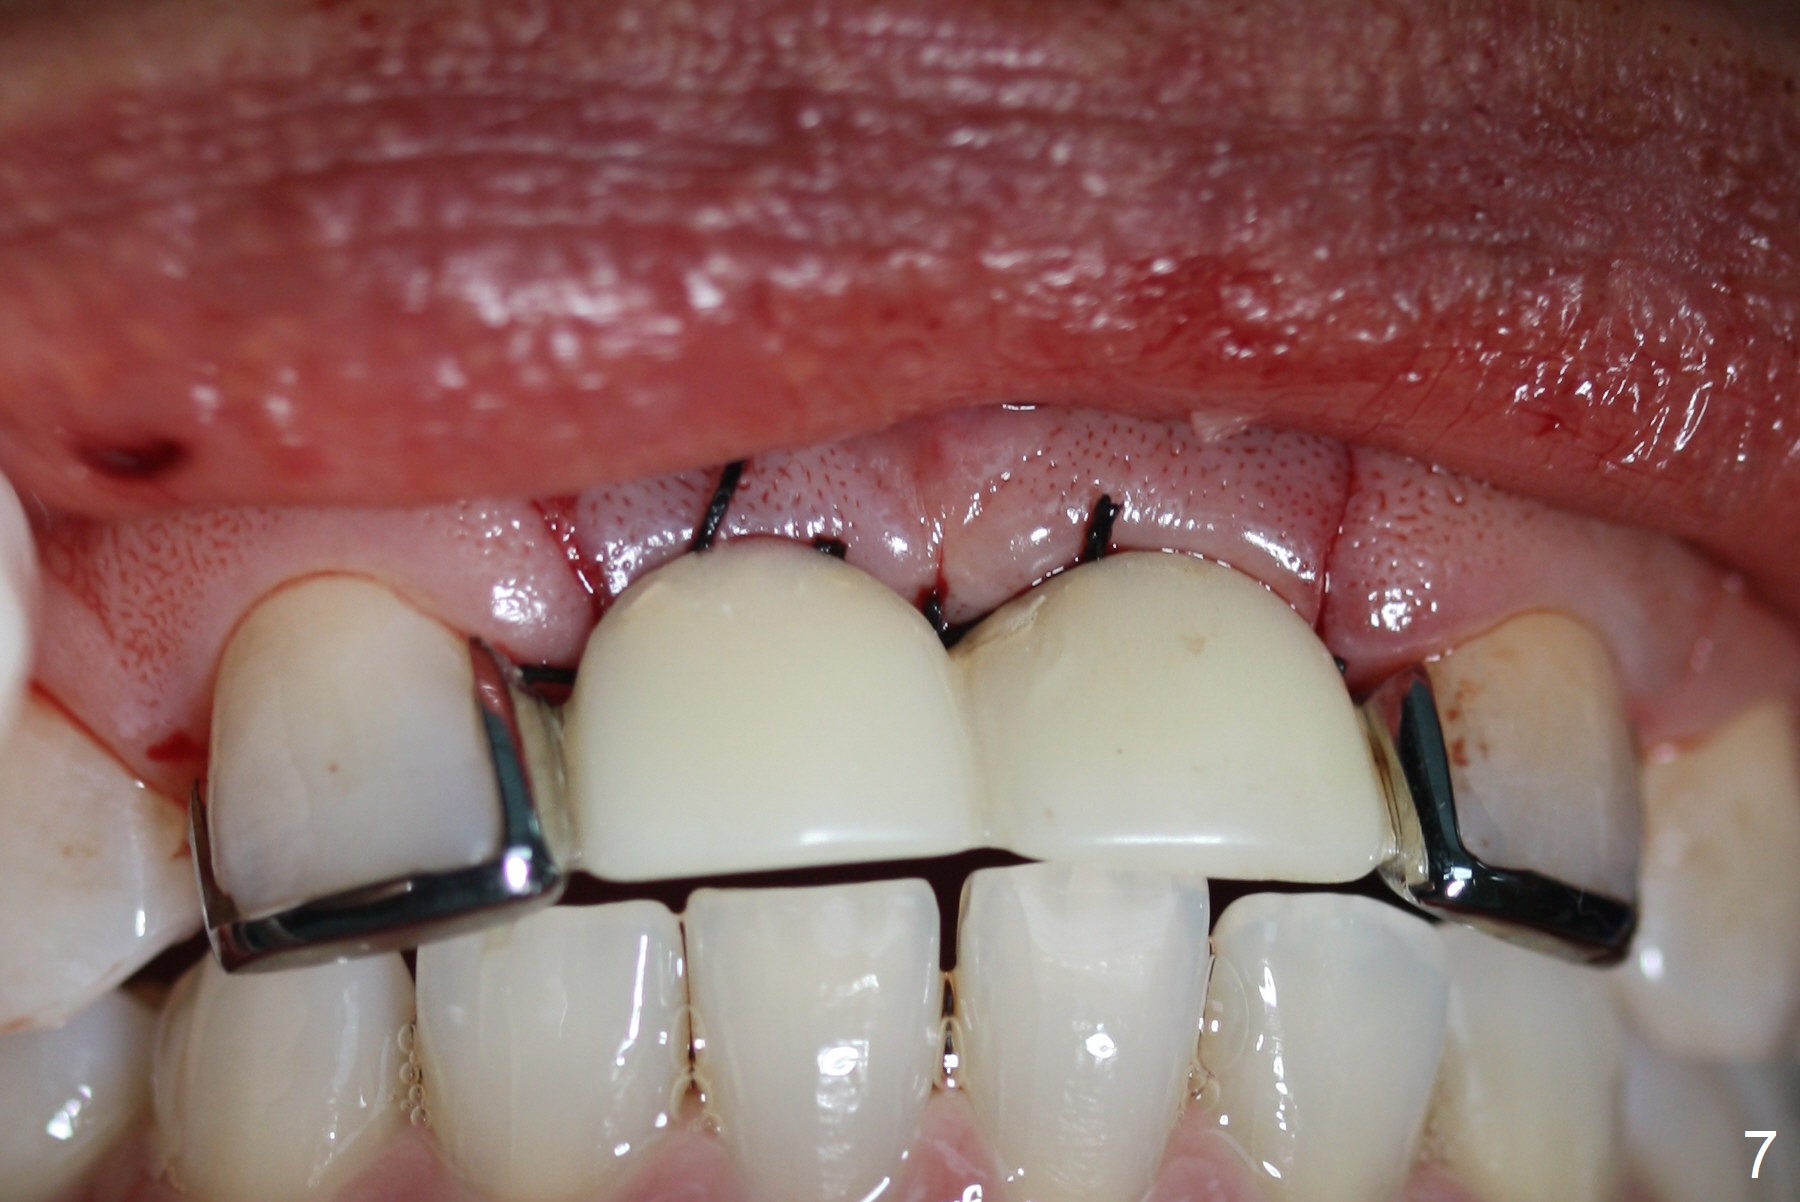

A 45-year-old Spanish woman requests implants to replace #7-10 FPD (Fig.1,2,7). After incision, osteotomy is initiated in the palatal aspect of the crest with 1.2 mm drill and DIO Bone Expanders (E1 (diameter 1.0/1.6 mm),E2 (1.3/2.3 mm), Fig.3,4). Following adjustment of the trajectory (to avoid invasion of the Incisive Canal (Fig.2 *) and use of E3 (1.7/3.1 mm), two of 3.5x11.5 mm HIOSSEN implants are placed with satisfactory stability (Fig.5). With Vanilla graft (Fig.5 *) placed over the palatally-exposed coronal threads, the flaps are approximated (Fig.6). The FPD is recemented temporarily (Fig.7).